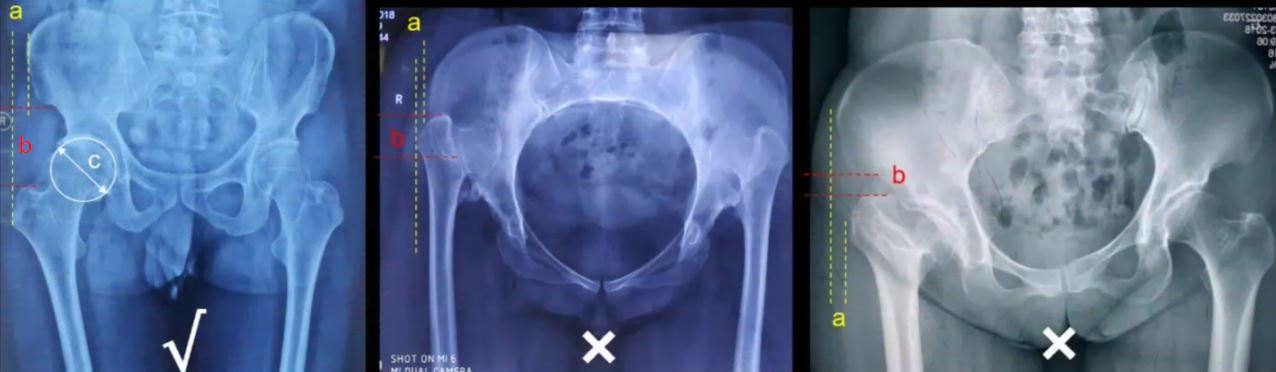

图3:大转子到髂骨翼外侧缘的距离(a)>0;髂前上棘-大转子间距(b)-股骨头直径(c)>0